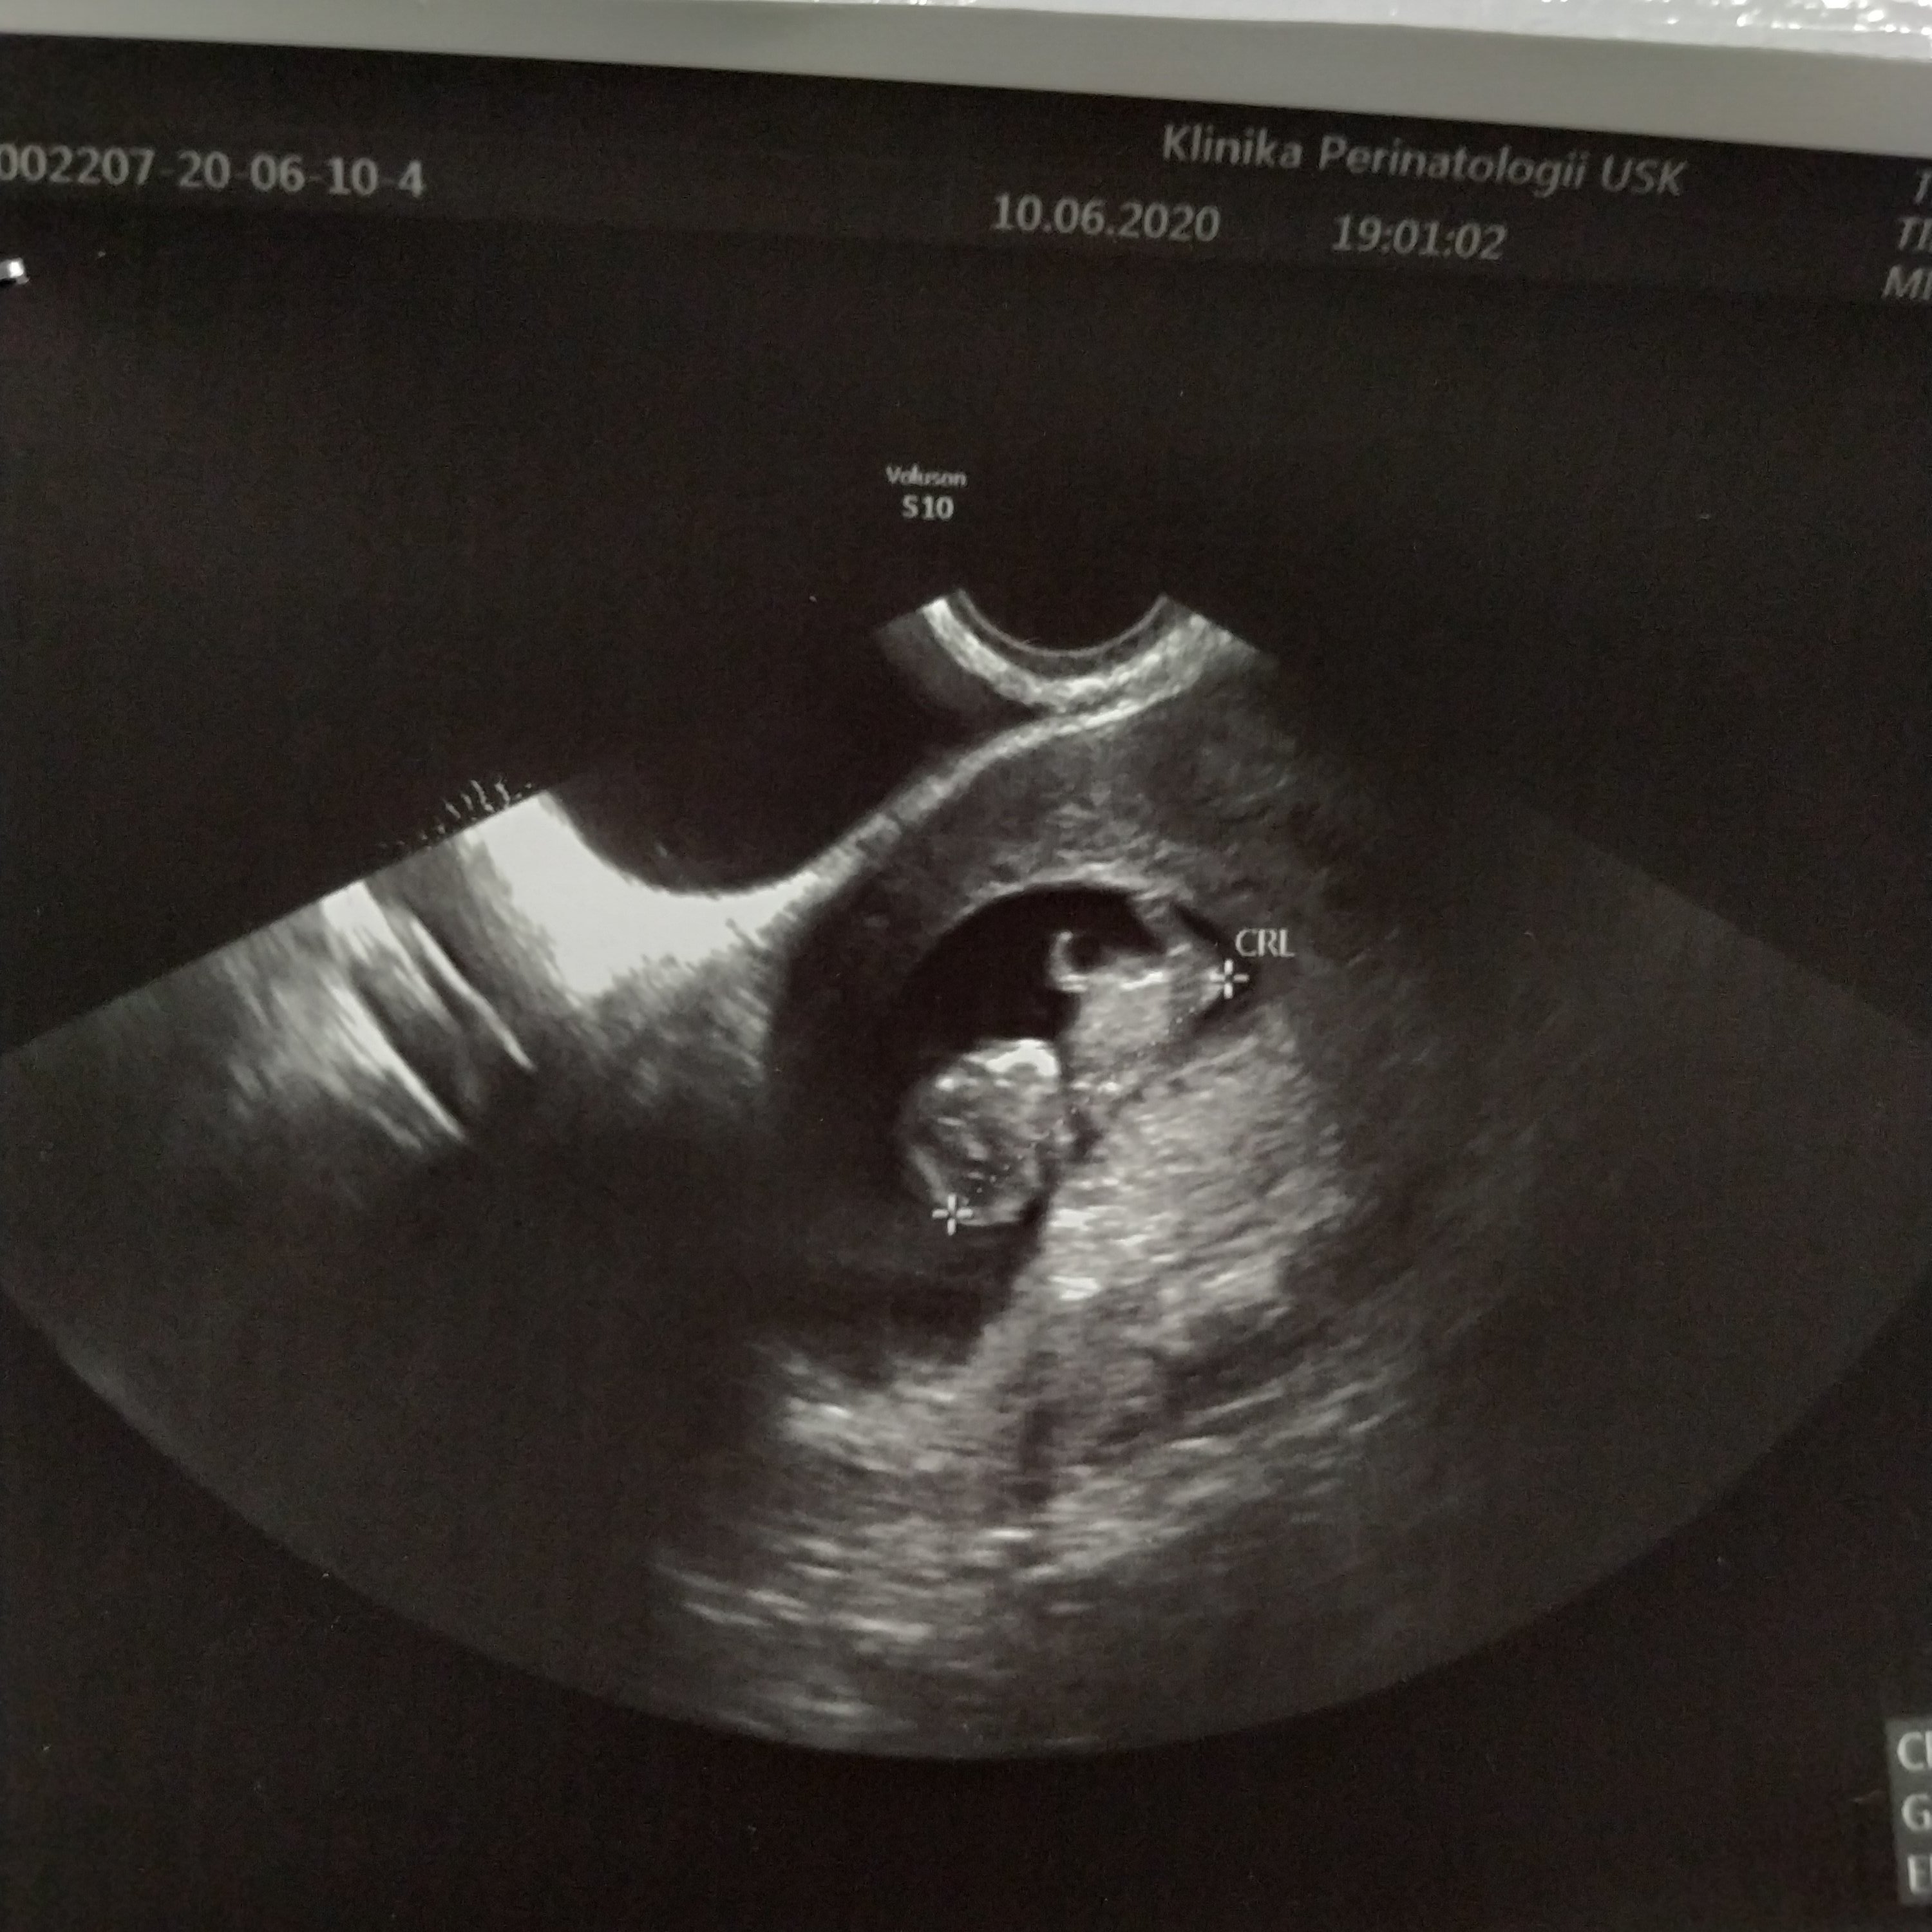

Dziewczyny dzisiaj prawie dostałam zawału jak wróciłam z pracy poczułam że mi strasznie mokro sprawdzam a tam taka ilość brązowego śluzu że aż słabo mi się zrobiło, a że jestem w ciąży wysokiego ryzyka ze względu na operację wycinania mięśniaków w zeszłym roku bez zastanowienie z drżącym sercem pojechałam na sor. Na miejscu lekarz bardzo skropulatnie mnie przebadał, uspokoił bo co prawda jest trochę starej krwi w macicy ale bardzo dokładnie wszystko obejrzał i mam tam kilka rozszerzonych naczynek i macica jest bardzo ukrwiona stad to plamienie, oszczędzać się bardziej mam i no spa 3 razy dziennie. Z dzieckiem wszystko dobrze, serducho bije 169 /min, kamień z serca ale co przeżywałam to nikomu nie życzę.to moje 3.30 cm szczęście❤️

Załączniki

• IMG_20200610_200840.jpg

IMG_20200610_200840.jpg

888,7 KB · Wyświetleń: 109